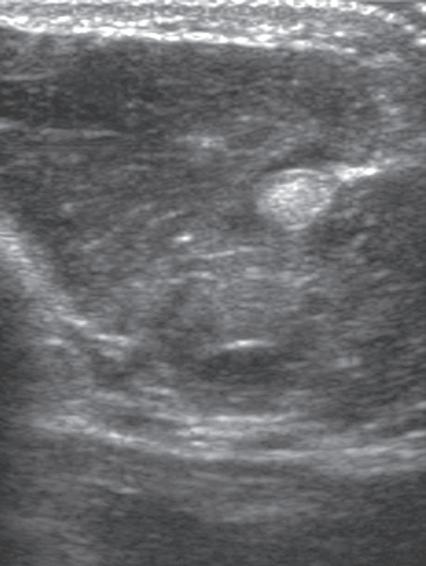

Another type of artifact is posterior acoustic enhancement or increased through-transmission. This occurs during imaging of fluid (Figs. 1.16 and 1.17) and some solid soft tissue tumors, such as peripheral nerve sheath tumors (see Fig. 2.59) and pigmented villonodular tenosynovitis (giant cell tumors of tendon sheath) (Fig. 1.18).10 In these situations, the sound beam is relatively less attenuated compared with the adjacent tissues; therefore, the deeper soft tissues will appear relatively hyperechoic compared with the adjacent soft tissues.7

FIGURE 1.18 Increased Through-Transmission. Ultrasound image of a pigmented villonodular tenosynovitis (giant cell tumor of the tendon sheath) (between × and + cursors) shows increased through-transmission (open arrows).